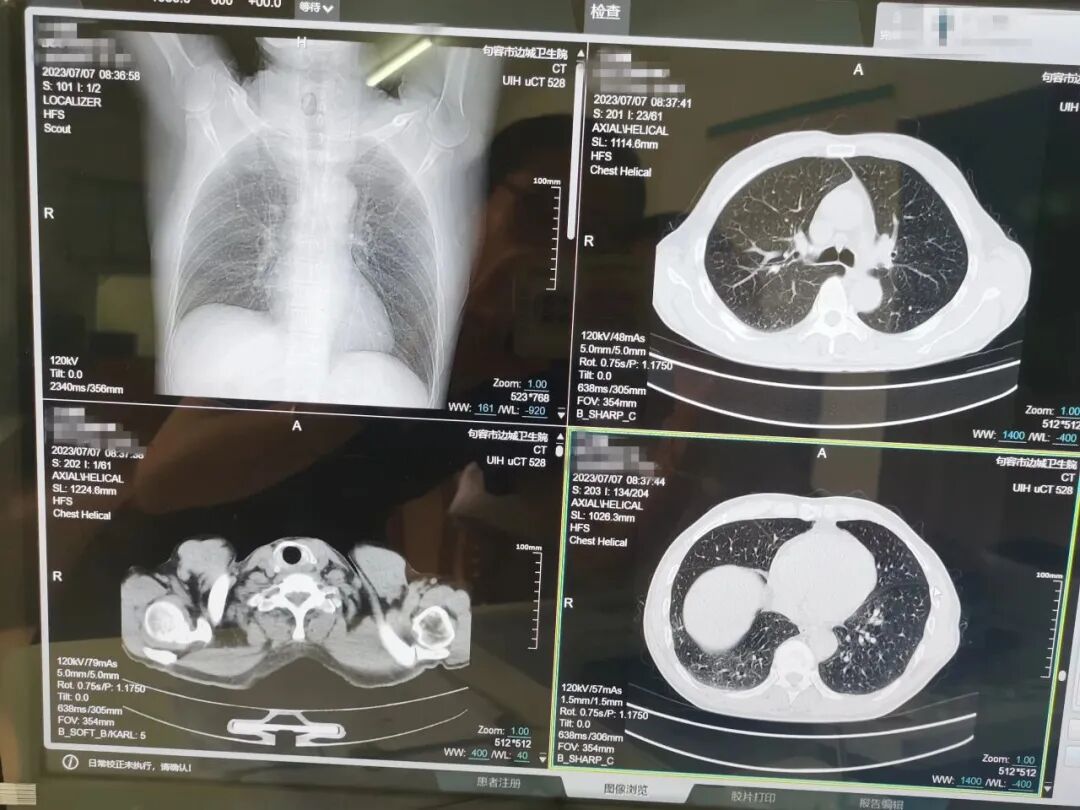

一起来看看

我院高端螺旋CT的扫描效果吧!

40排时空影像链,0.55mm业内最薄层厚:相比常规16排、32排的0.625mm,可提升120%的乙轴图像精准度,对胸部早期病灶、隐蔽性病灶检出率更高。